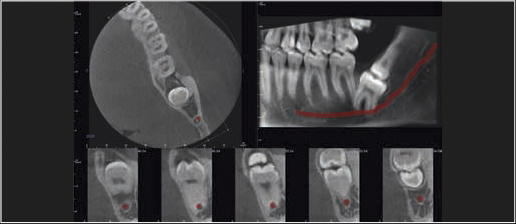

Tomografia komputerowa jest niezastąpiona w planowaniu leczenia implantologicznego i chirurgicznego. W wielu przypadkach pozwala uniknąć powikłań podczas leczenia kanałowego jeszcze przed jego rozpoczęciem. Wysokiej rozdzielczości badanie mikroCBCT (endoCBCT) precyzyjnie obrazuje architekturę systemu kanałowego zęba. Na jego podstawie lekarz może ocenić ilość kanałów, ich krzywiznę oraz ewentualne połączenia.

Precyzyjna diagnostyka z polem obrazowania 5 x Ø5 cm i rozdzielczością 85 μm (TRYB ENDO).

Szczegółowa analiza systemu kanałowego zębów oraz tkanek przyzębia.

Cztery różne pola obrazowania zapewniają niezawodną diagnostykę 3D w całym obszarze jamy ustnej. Zapewniają one precyzyjne dopasowanie, odpowiednie do wskazań a także uniwersalne możliwości zastosowania w codziennej praktyce – od endodoncji, poprzez implantologię do chirurgii jamy ustnej.